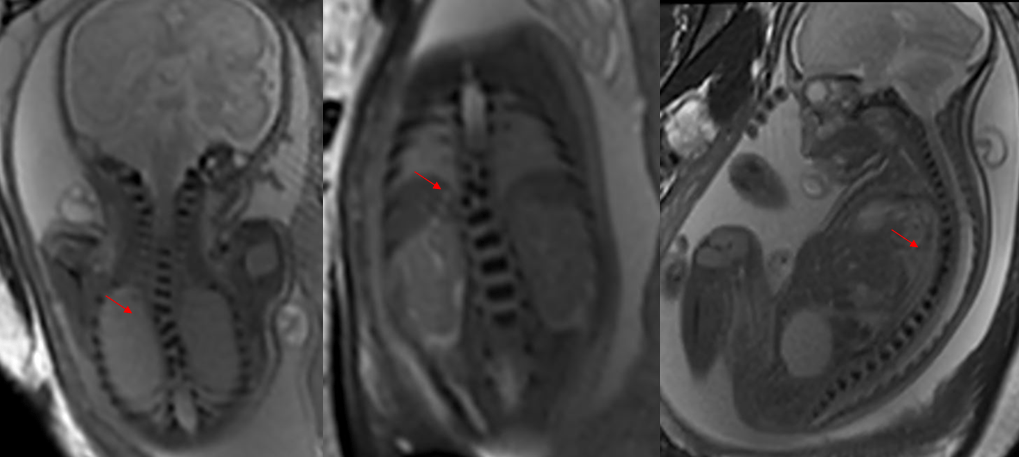

临床资料:孕28.5周;超声提示胎儿脊柱椎体回声异常

影像诊断:胎儿胸椎多个椎休发育不良伴脊柱侧弯